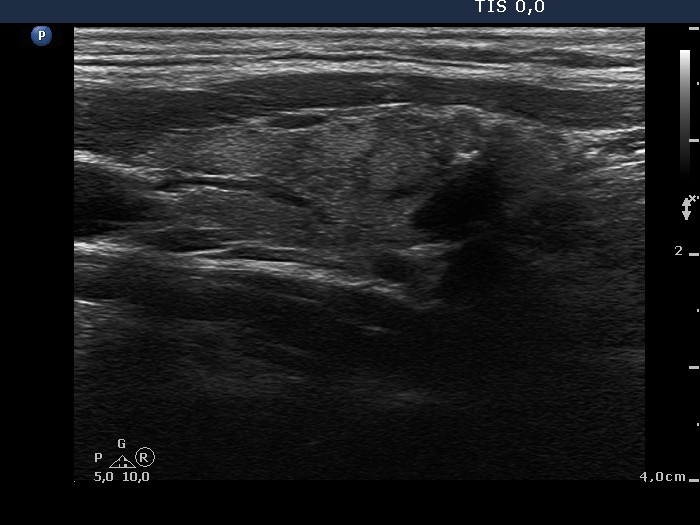

100 consecutive cases of papillary cancer - case 039 (ultrasonographic picture 5)

Left lobe, longitudinal scan. There is a lesion in the lower two-third of the lobe. The borders are irregular. Note the presence of non-specific granules and more bright microcalcifications.